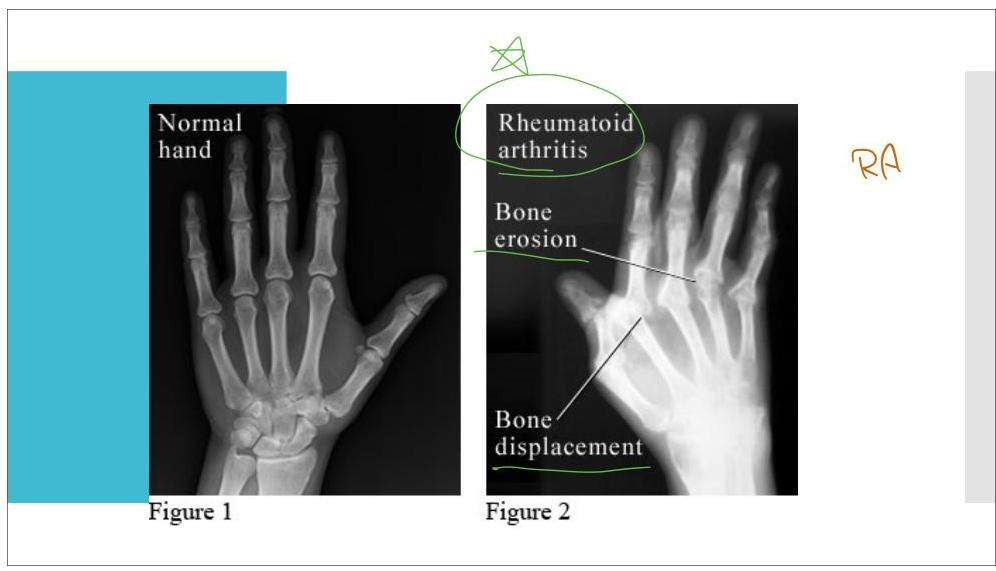

Rheumatoid arthritis

- Contributary factors:

- Interplay between several genetic factors (HRLDRB1 and others)

- Environmental factors (Smoking)